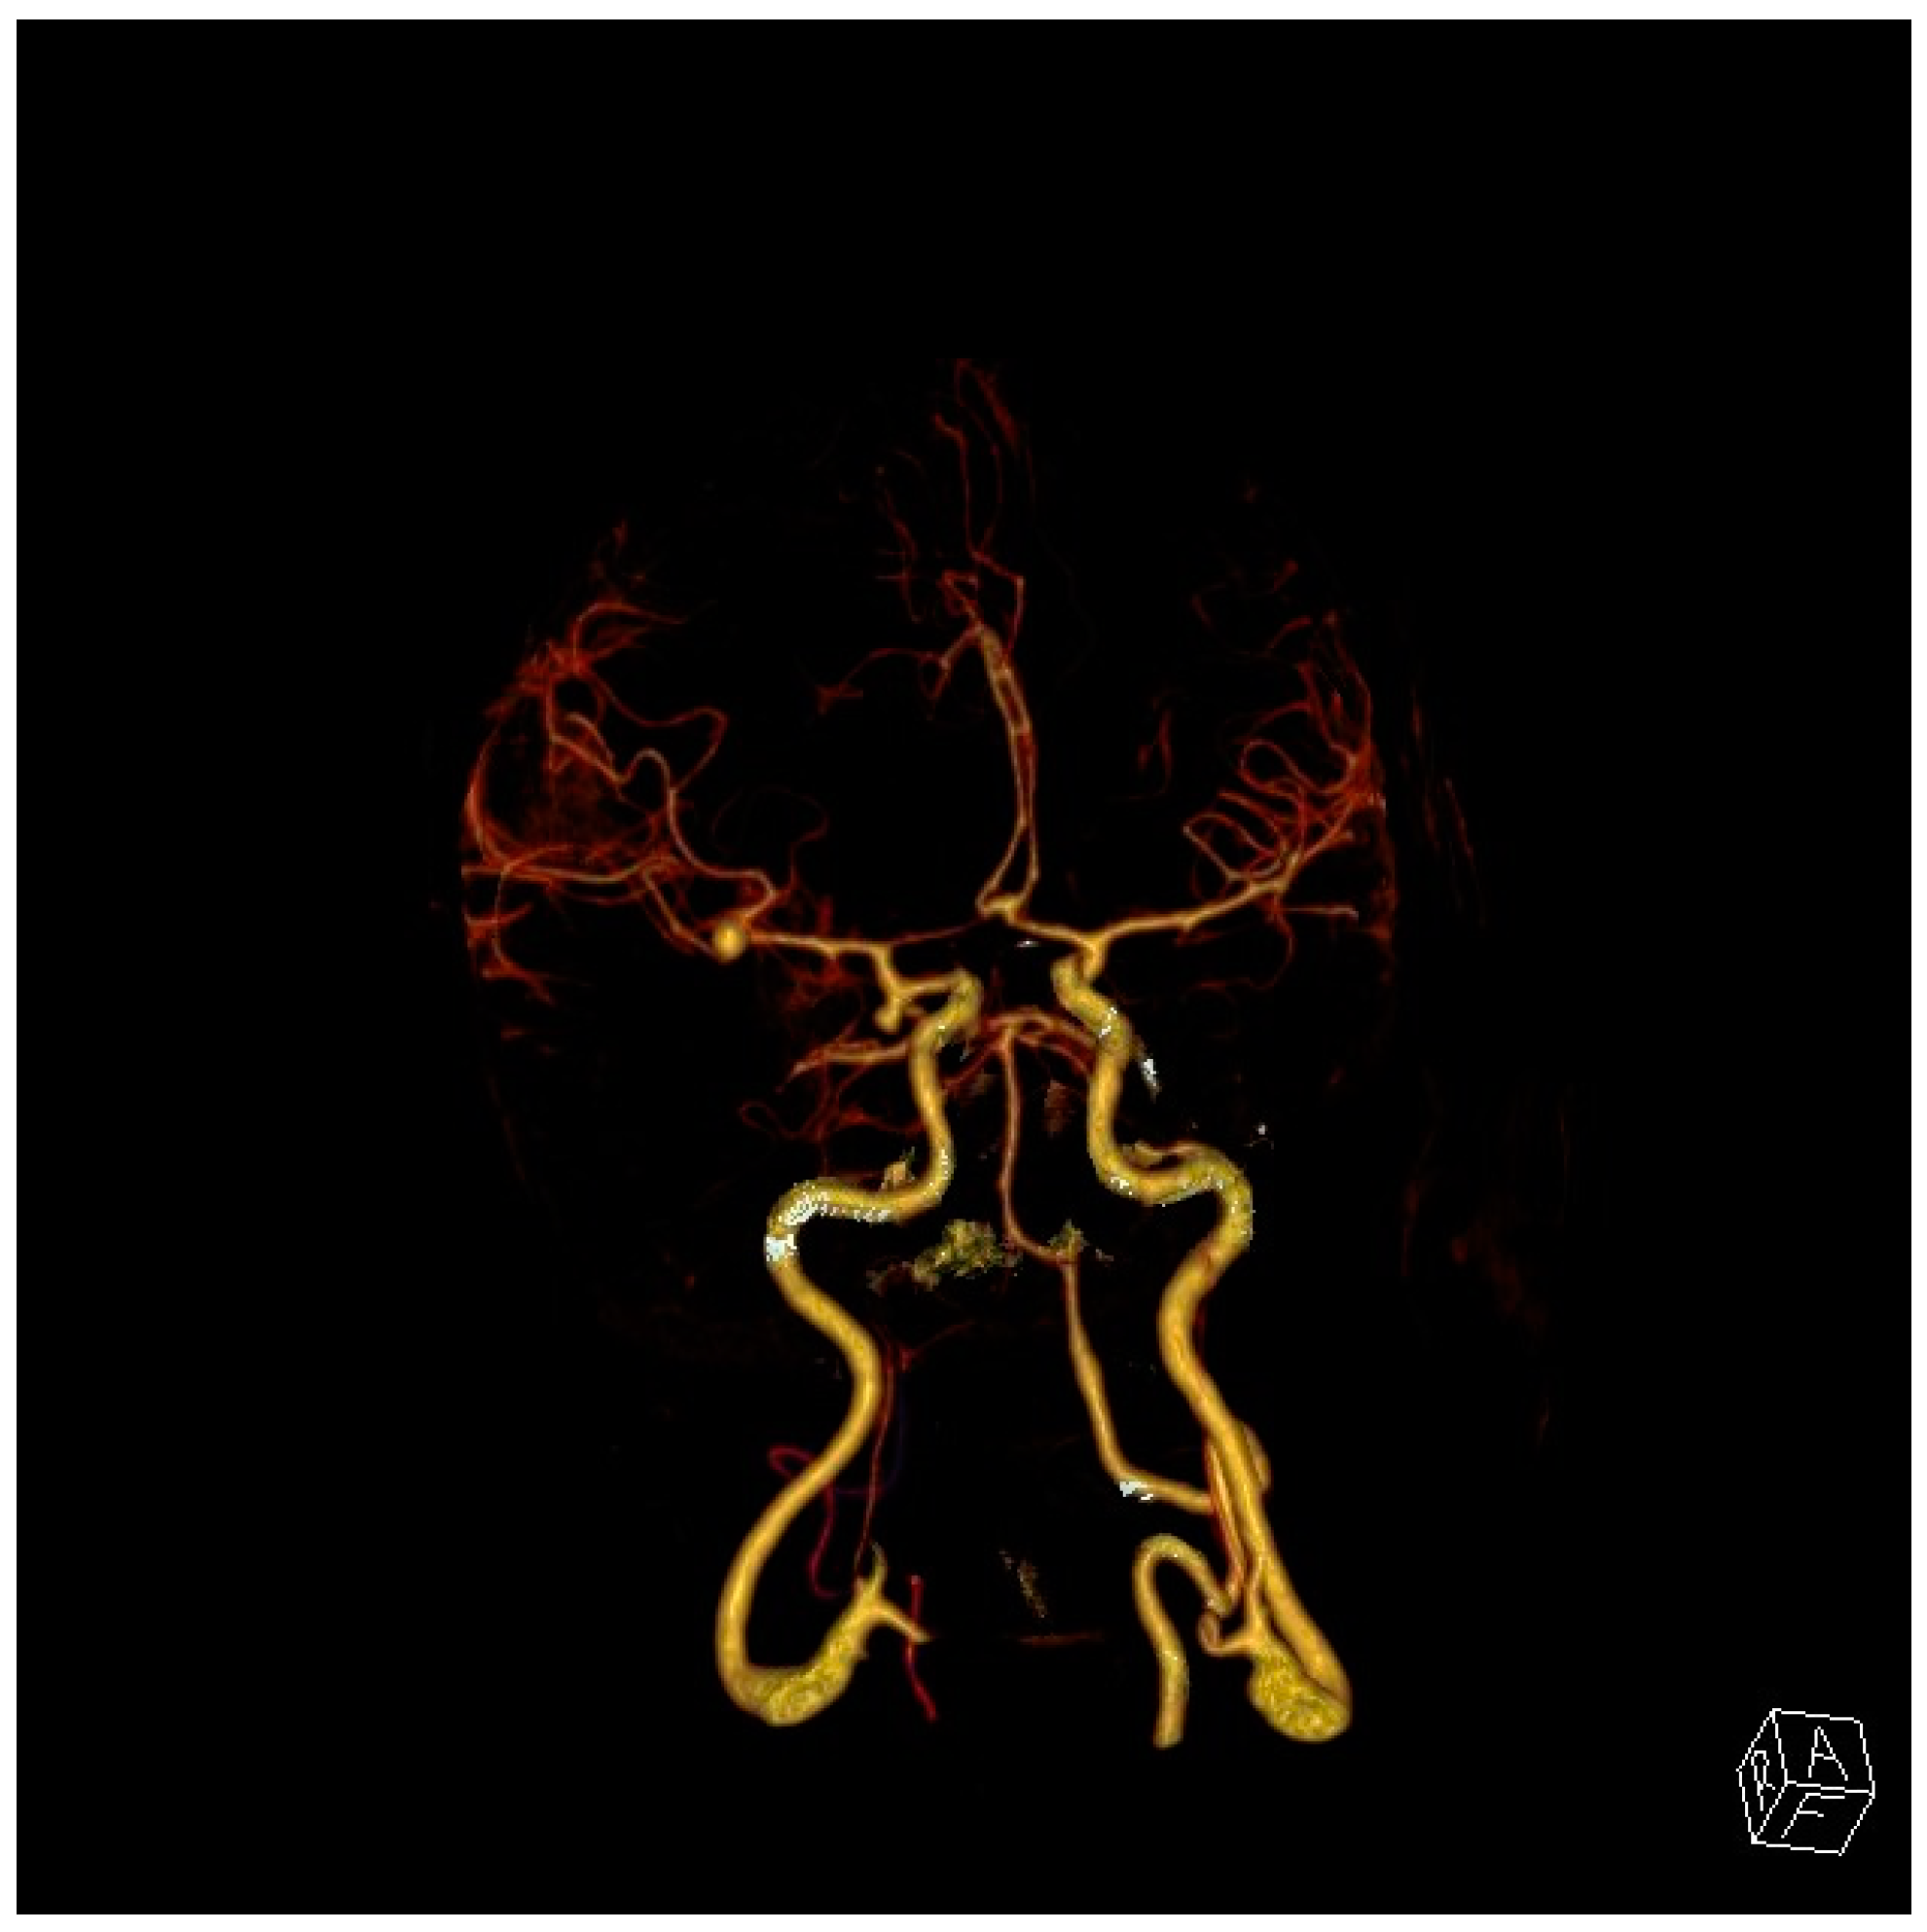

5. Diagnosis